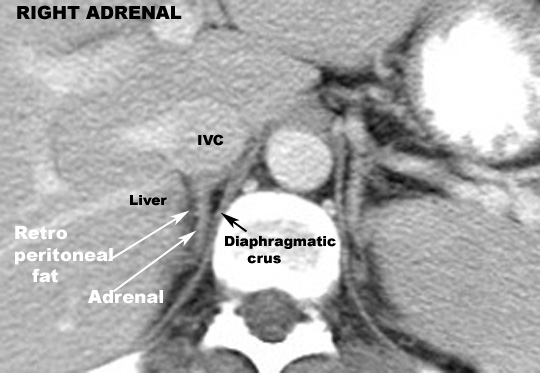

Identify the structures around the diaphragmatic crus. Click the image for labeling.